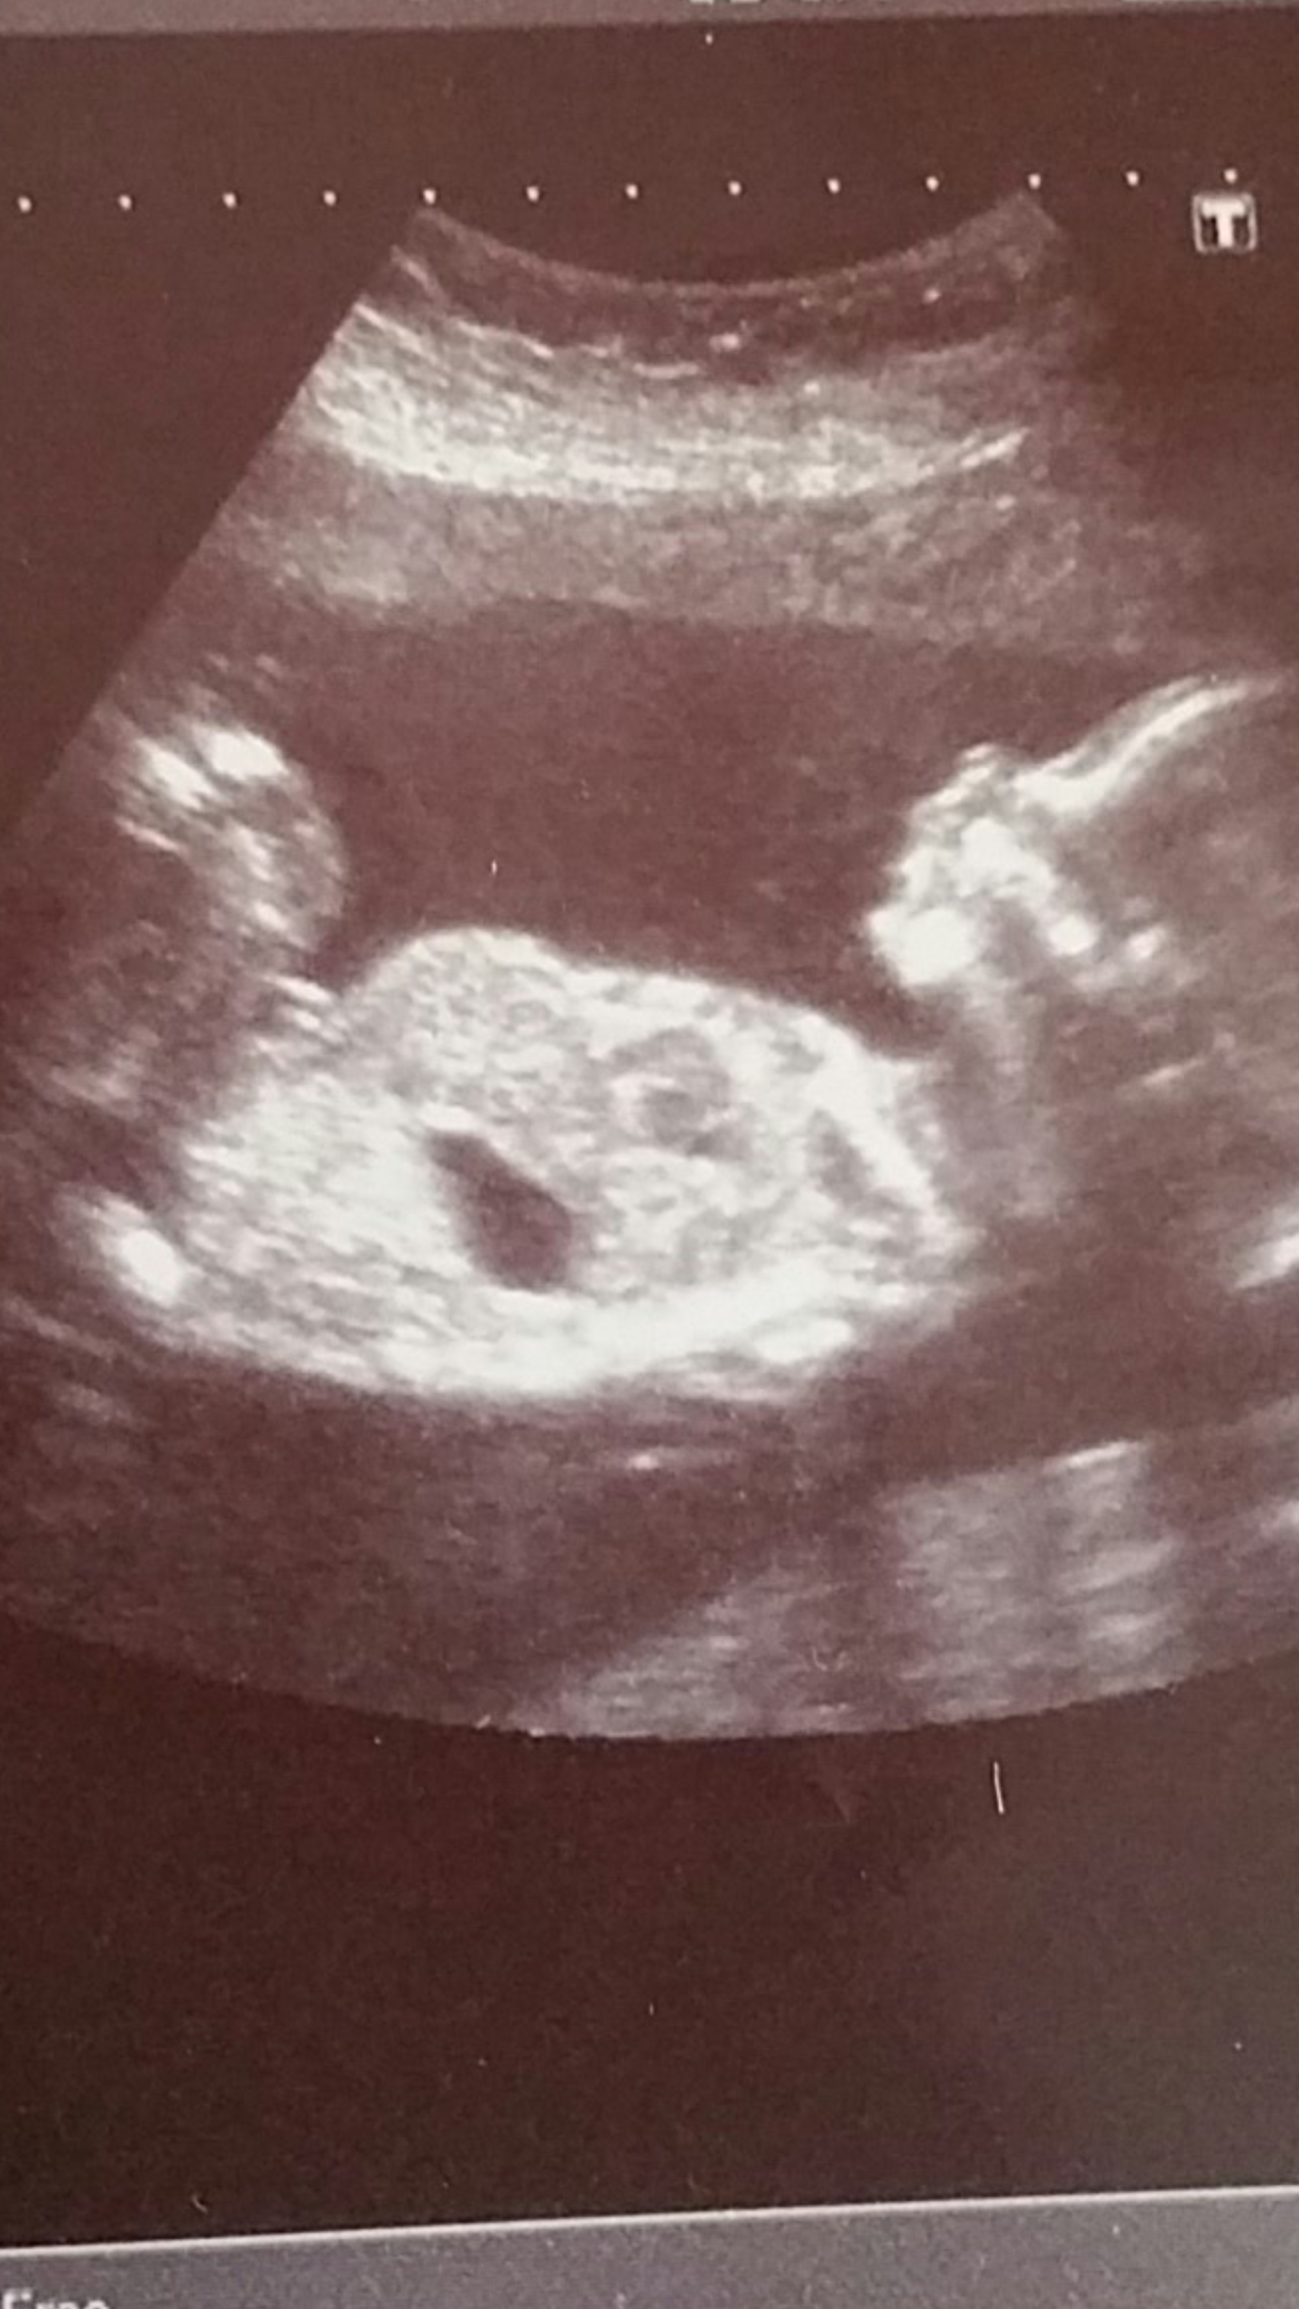

We went to our anatomy scan today and I was sure I saw a penis on the screen but it seemed too big (maybe the umbilical cord?). My husband told me he thought he saw it too. We have been adamant that we aren't going to find out, so the doctor and technician kept it a secret, but now my curiosity has gotten the better of me. Looking at the picture, I'm thinking I see a penis, or is that something else.....